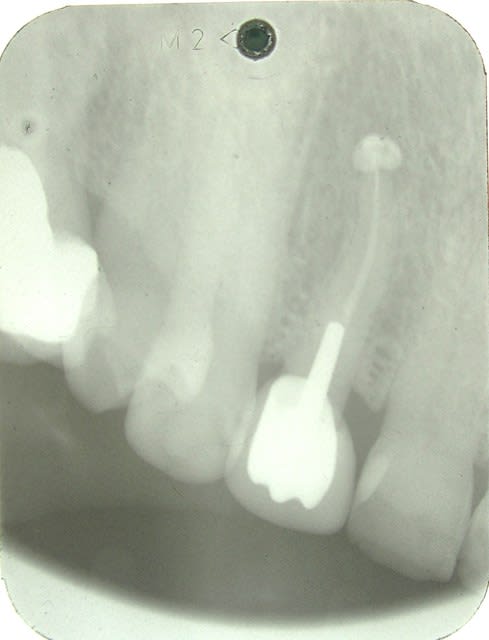

controle du cas de la page 19 , ce jour .

faut aimer l'aspect champignon , mais ça va , chance !!!!

11.12 - Eugenol

oui ca avance... enfin.....tu aurais dû sous-exposer la rx encore un chouia et là on aurait dit que c'est carémment cicatrisé.

voilà ,j'ai repris la photo de la meme radio , ce qui ne change pas le fait qu'elle soit tjs sur l'arcade :-)